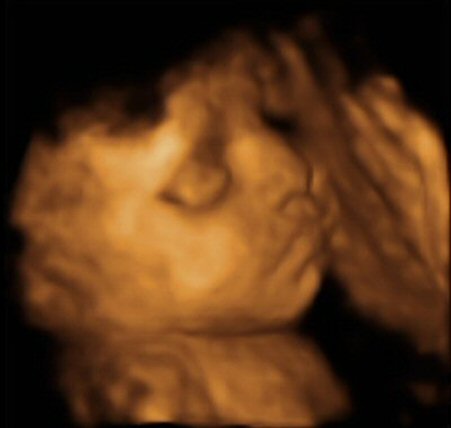

- 29 week 4D scan

- The scan photos shown below are 3D images from the babybond 4D scan at 29 weeks gestation.